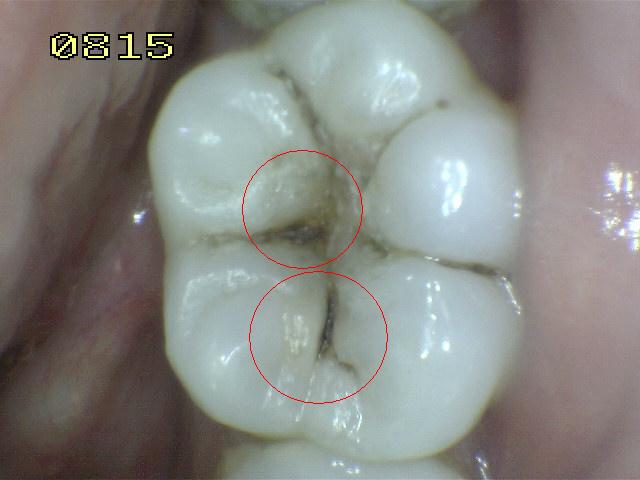

Código 5

Código 4